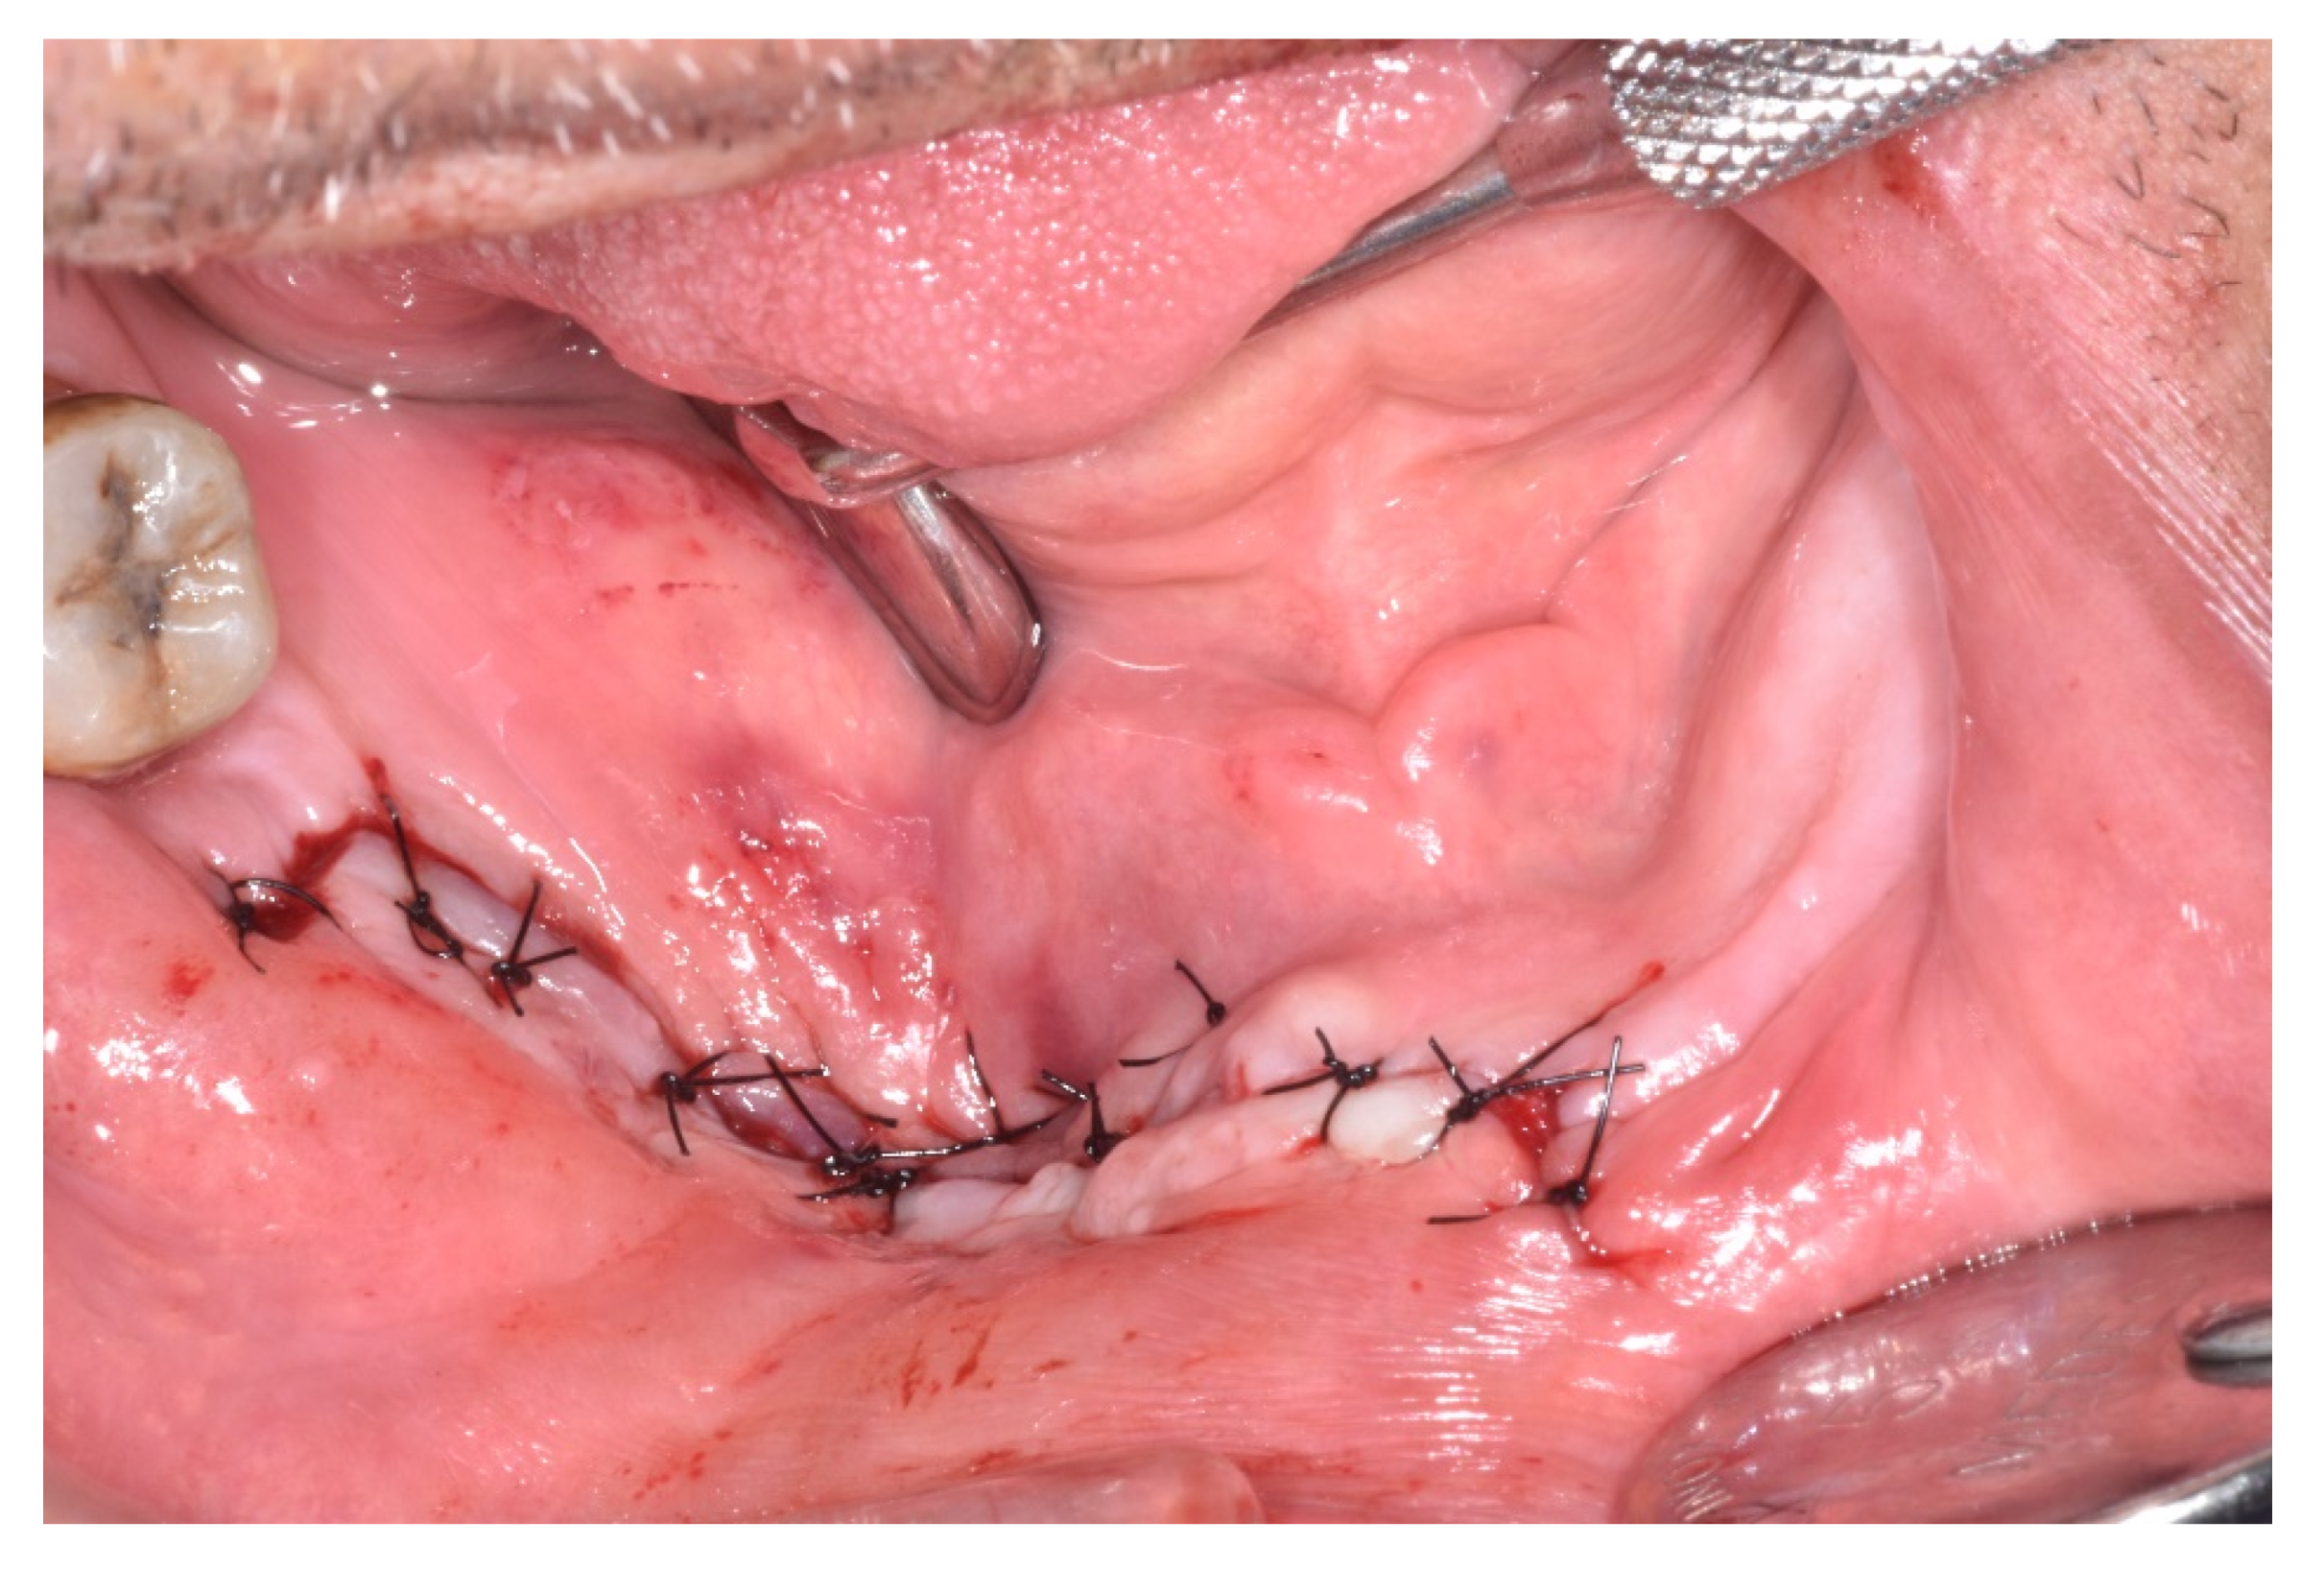

| Treatment | ||||||||

| Medical | x | x | x | 3 | 6 | |||

| Surgical | x | x | x | 3 | 10 | |||

| Procedure | ||||||||

| Debridement | 3 | |||||||

| Sequestrectomy | x | 1 | 1 | |||||

| Saucerization | 3 | |||||||

| Submarginal resection | x | x | 2 | 3 | ||||

| Outcome | ||||||||

| Spontaneous expulsion of sequestrum | x | 1 | ||||||

| Healed | x | x | x | x | 4 | |||

| Partially healed | ||||||||

| Unchanged | ||||||||

| Progressive | x | 1 | ||||||